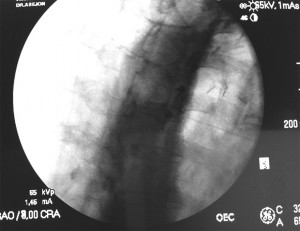

Por último se comprueba la localización de la aguja con una imagen en lateral, la cual debe estar colocada en la línea facetaria, siempre posterior al agujero foraminal. Si la técnica es con RF se debe comprobar también con estimulación motora (2Hz con 1ms de amplitud de pulso y 1V o menos), con ésta se debe conseguir una contracción discreta de los músculos paravertebrales. Luego se aplica estimulación sensitiva (50Hz con 1ms de amplitud de pulso y 0.5V), con ésta se busca conseguir una parestesia.

Para la visualización se coloca el rayo en PA y se identifican los cuerpos vertebrales, luego se alinea el doble contorno de la parte inferior del cuerpo movilizando el rayo en dirección cráneo-caudal. A continuación se buscan los procesos transversos. El punto de entrada se marca en el margen inferior de la misma vertebra desde T1 hasta T5, y en el borde superior del pedículo inferior si el bloqueo se va a realizar desde T6 hasta T10.

Se esteriliza el campo de trabajo y se avanza una aguja 22G de 10cm de longitud con un ángulo de 60° en dirección cefálica hacia el proceso articular superior. La aguja debe seguir una línea vertical imaginaria que conecte la porción media de los pedículos superior e inferior y hacer contacto siempre con el hueso. Hay que evitar que la aguja quede apoyada en la parte medial del aspecto medial del pedículo en la proyección PA, esto previene una inyección inadvertida en el espacio epidural o subaracnoideo. El rayo se gira 20°-30° en oblicuo hacia el lado contralateral hasta que la línea articular sea visible, la punta de la aguja debe estar en la parte inferior de la articulación para que pueda entrar fácilmente a la cápsula. Para comprobar que está intraarticular se inyectan 0.1-0.2ml de contraste, después de lo cual se debe ver la articulación y el receso inferior y/o superior.